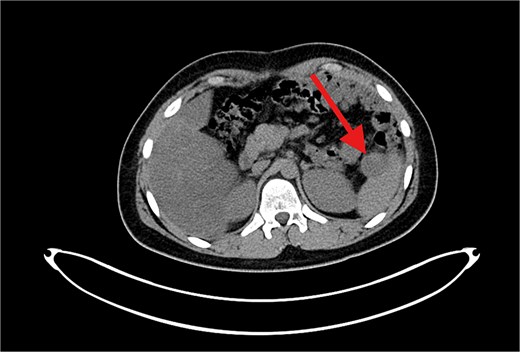

Contrast-enhanced axial CT image showing a large, heterogeneously enhancing soft tissue mass measuring ⁓11 × 5.5 × 8.3 cm in the left subphrenic region, abutting, and indenting the greater curvature of the stomach. The lesion demonstrates internal cystic and necrotic components, consistent with a recurrent undifferentiated embryonal sarcoma.